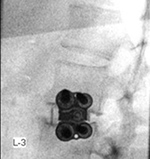

| Zero-Profile lumbar fixation L2-L4 |

| 45 year-old woman with L2-5 anterior lumbar interbody fusion (ALIF) for low back pain. The lateral views are respectively in neutral and flexion positions. The CT images are selected slices in the coronal and sagittal planes, respectively. |

| 45 year-old woman with L2-5 anterior lumbar interbody fusion (ALIF) for low back pain. |